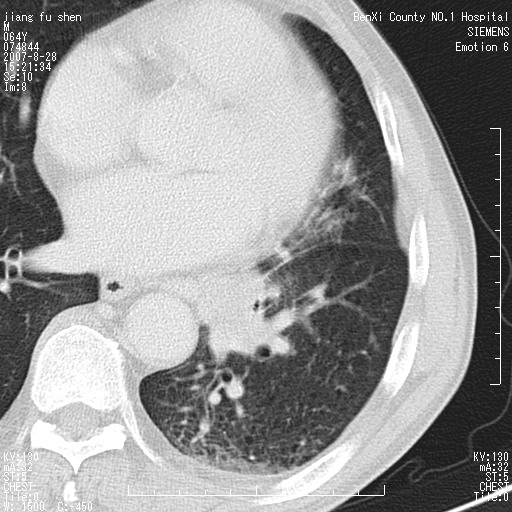

男、64、咳嗽、发烧一周、左肺呼吸音稍弱。既往肺结核,右手结核。

本次扫描患者未带原片,左肺下叶发现病灶。左肺上叶空洞,5组淋巴结肿大,1cm左右。

追问病史三月份ct扫描左肺上叶空洞,医大诊断肺结核。

平扫20-33hu

增强31-33hu

1分半44-52

2分55-67

左肺下叶前内基底段支气管明显偏心性狭窄,周围分叶状肿块,伴有阻塞性肺炎,支持肺癌可能性大。

考虑左肺中央型肺癌并阻塞性肺炎

病灶边缘可见多量较长棘影及纤维条索状影,除外病灶边缘较光整,病灶有分叶表现,但多表现为较浅分叶,且向周围伸出之叶多呈尖角改变,且边缘较光整,病灶增强呈中度延时增强,且早期及中期仅轻度增强,结合患者病史,多考虑继发型肺结核,炎性增殖灶形成,不除外肺癌